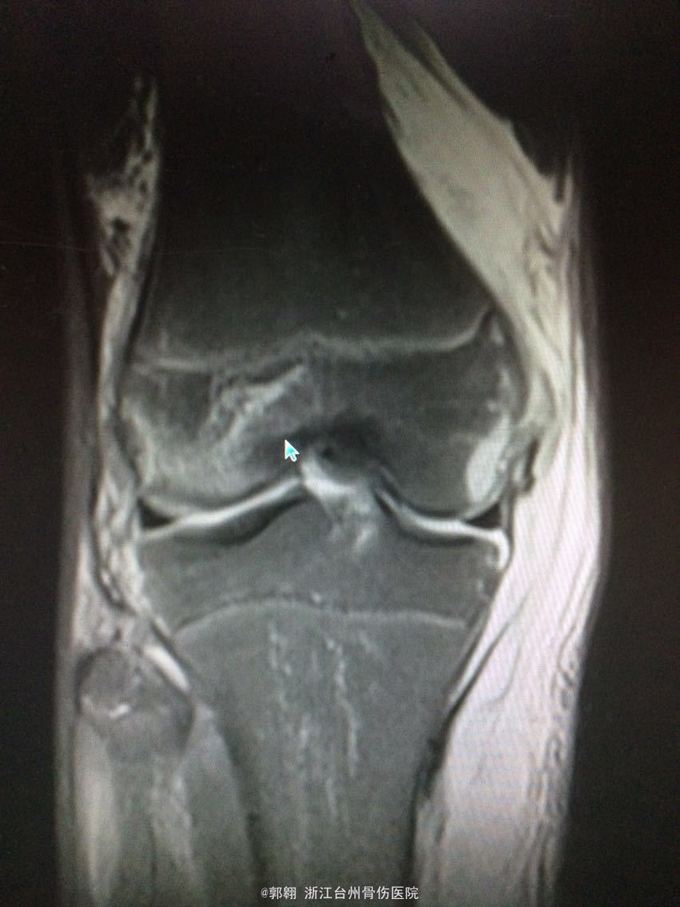

右膝关节跑步摔伤疼痛功能障碍3小时 病史:患者15岁 上体育课时跑步摔倒致右膝关节畸形疼痛 功能障碍,由老师送至医院就诊。

查体:右膝关节及小腿上段肿胀明显,张力较大,压痛位于内侧副韧带股骨处和膝关节外侧,膝关节波动感,浮髌试验阳性、扳膝试验阳性、抽屉试验阳性、Lachman阳性、膝关节屈伸活动因疼痛而障碍,足背动脉波动良好。 MRI:右膝关节股骨内髁骨折 胫骨平台外侧缘骨折

诊断:右膝关节内侧副韧带撕裂 前交叉韧带损伤 股骨内侧髁骨折胫骨平台外侧缘骨折 腓肠肌肌肉拉伤 处理:制动 支具托固定 冰敷 退肿止血药物治疗